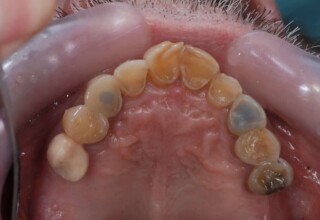

Extensive case with crowns in almost all teeth

Extensive case with crowns in almost all teeth due to extensive wear, old restorations, posterior root canals and aesthetic concerns. Patient (60years old) presented with intense bruxism which he never had treated. Consequently, he obtained very deep cervical abrasions which jeopardized tooth integrity. Restorations (fillings) were executed mainly with adhesive resinous materials and three custom cast post and cores. Temporary crowns were placed to evaluate the desired size, shape and position of the teeth before permanent crown fabrication.